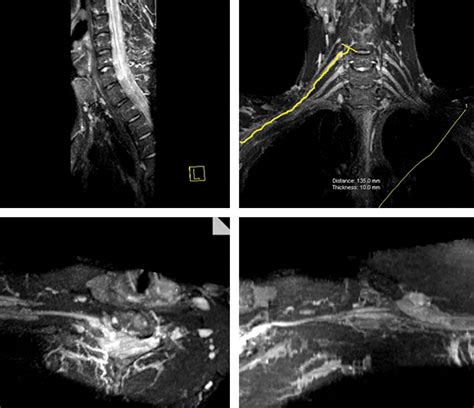

To overcome this, this specialized imaging employs specific pulse sequences designed to suppress the signal from fat—which often obscures nerve detail—while enhancing the signal from water-rich tissues like nerves. This process effectively makes the nerves "light up" on the resulting images, allowing radiologists to assess their anatomy, signal intensity, and trajectory in high detail.

• Sciatica and Radiculopathy: Identifying nerve root compression caused by herniated discs or other structural anomalies.

During the exam, the patient is positioned in the MRI scanner. If the area being imaged is in a limb, specialized coils—devices that help capture the radiofrequency signals—are placed around that specific body part to maximize image quality. In some cases, contrast dye may be administered intravenously to further enhance the clarity of the images, especially if a tumor or inflammatory process is suspected.

Once the images are acquired, they are analyzed by a radiologist with specialized expertise in musculoskeletal or neuroradiology. The goal is to identify changes in the nerve's appearance. For instance, a healthy nerve typically appears as a thin, uniform structure with a consistent signal. In contrast, an injured or compressed nerve may exhibit:

• Increased signal intensity: Often indicative of edema (swelling) or inflammation within the nerve.

• Nerve enlargement (fascicular thickening): A sign that the nerve is being subjected to chronic pressure or trauma.